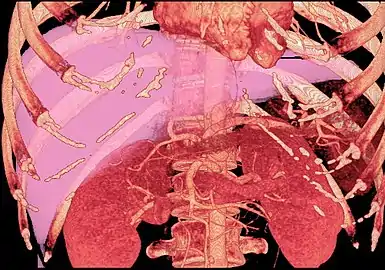

MDCT image. Arterial anatomy contraindicated for liver donation

MDCT image. Arterial anatomy contraindicated for liver donation MDCT image. Portal venous anatomy contraindicated for liver donation

MDCT image. Portal venous anatomy contraindicated for liver donation MDCT image. 3D image created by MDCT can clearly visualize the liver, measure the liver volume, and plan the dissection plane to facilitate the liver transplantation procedure.

MDCT image. 3D image created by MDCT can clearly visualize the liver, measure the liver volume, and plan the dissection plane to facilitate the liver transplantation procedure. Phase contrast CT image. Contrast is perfusing the right liver but not the left due to a left portal vein thrombus.

Phase contrast CT image. Contrast is perfusing the right liver but not the left due to a left portal vein thrombus.